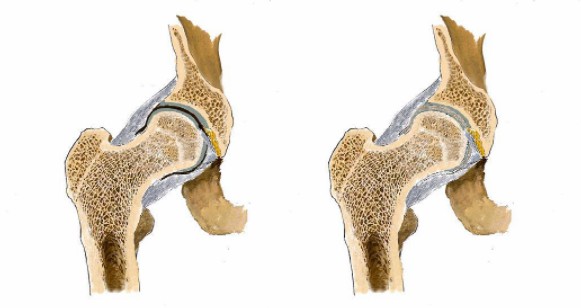

看男孩不說話,醫(yī)生繼續(xù)說道:“你的HLA-B27顯示陰性,如果是陽性就可以確診是強直性脊柱炎,現(xiàn)在只能排查……如果確診是強直性脊柱炎,就要就要及早治療,因為這個病是不可逆的,我們只能延緩它病程進度……”

醫(yī)生對著拍好的片子來來回回看了好幾遍,男孩就一直站在他邊上,他知道醫(yī)生接下來說的話將決定自己的一生。

“你這沒事!腿痛就是有點水腫炎癥導致的,注意休息鍛煉適度就會好的。”